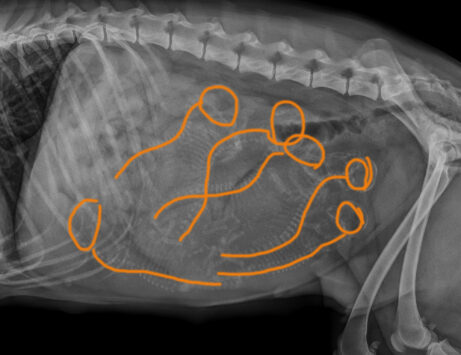

Kedy je najvhodnejší čas na USG? Aké sú mínusy, ak na USG pôjdete príliš skoro alebo príliš neskoro? Je USG škodlivé pre šteniatka alebo suku? Ako dokážeme spoľahlivo spočítať šteniatka pomocou USG vyšetrenia? Je RTG vyšetrenie na počet šteniat pred pôrodom užitočné? Škodí nejako matke alebo šteniatkami? Kedy je najvhodnejšie ho vykonávať ? Má aj svoje nevýhody?